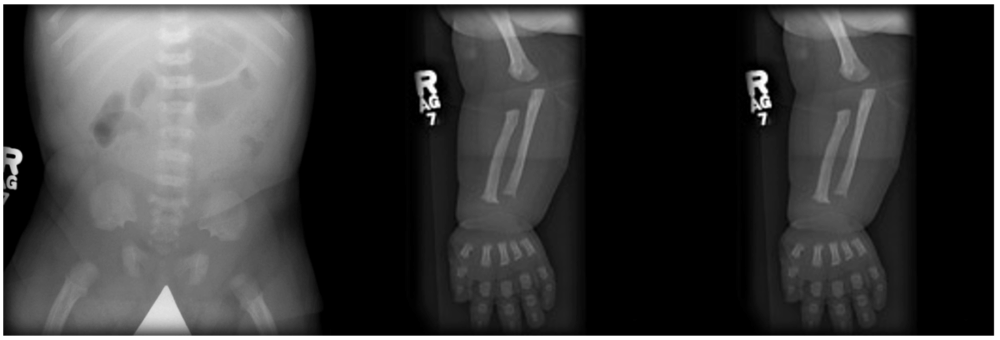

- Patients with achondroplasia are typically short-statured with poor muscle tone and loose joints. They have shortened arms and legs (rhizomelia), with prominent shortening of proximal limbs when compared to distal. Those affected have an average torso size, and their sitting height may be within normal limits, but their standing height will often be below the 5th percentile.5

- They also have varus deformities of the legs with flat feet that are short and broad. This deformity is structurally complex, originating from a combination of internal tibial torsion, lateral bowing, and some dynamic instability and laxity of the knee.

- They may present with limited elbow extension. A prominent gap between the middle and ring fingers (trident hand) with short digits (brachydactyly) is a common finding.

Figure 1. Plain radiographs of the upper and lower limbs demonstrate shortened long bones. The lumbar spine has a decreased transverse diameter. The iliac wings have a tombstone morphology. Gaillard F, Walizai T, Ranchod A, et al. Achondroplasia. Reference article, Radiopaedia.org. Accessed on 24 Sep 2025. Link